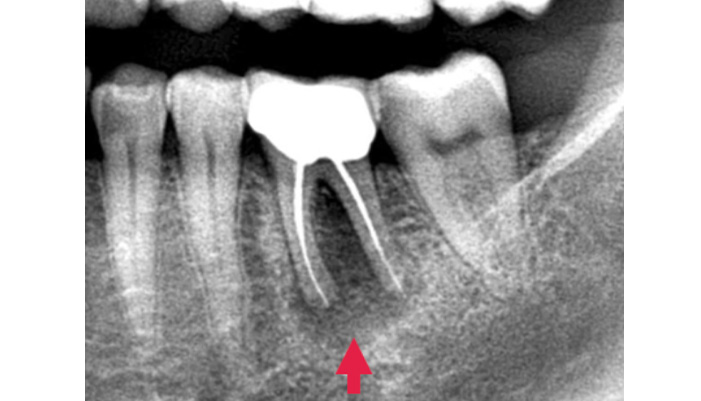

治療前

患者様は「何度も腫れる」「根の治療を繰り返している」とのお悩みで来院されました。診査の結果、歯の根の先に膿の袋(根尖病変)が確認され、過去の治療で細菌が十分に取り除けていない可能性が考えられました。そこで、ラバーダムを使用して治療部位への細菌の侵入を防ぎながら、拡大視野下で精密な根管治療の再治療を行い、感染源の徹底的な除去を行いました。

| 主訴 | 右下が腫れて痛い |

|---|---|

| 治療期間 | 1ヶ月 |

| 治療費 | 保険適用 |

| 治療内容 | レントゲンで確認すると、根尖病変が認められ根管治療を行いました。 |

| 治療のリスク | 再発が起きる場合は、外科処置を追加で必要なケースがあります。 |